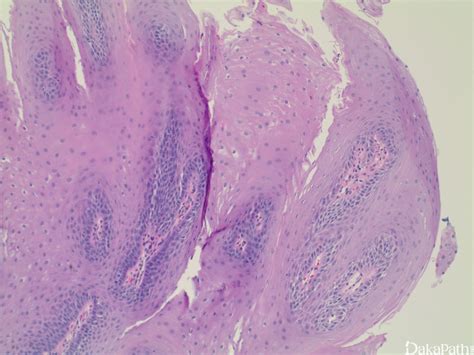

3、乳腺外形改变:可见肿块处皮肤隆起,有的局部皮肤呈橘皮状,甚至水肿、变色、湿疹样改变等。

4、乳头近中央伴有乳头回缩。乳房皮肤有轻度的凹陷(医学上叫做“酒窝症”),乳头糜烂、乳头不对称,或乳房的皮肤有增厚变粗、毛孔增大现象(医学上叫做“橘皮症”)。

2、皮肤改变:常表现为浅表静脉怒张,酒窝征和桔皮样皮肤。

重庆现代女子医院乳腺专家说:乳腺肿块的可能性有很多,如果在乳房处摸到一个无痛性的小肿块,肿块的表面坚硬、疙里疙瘩、边界不清,随后发现肿块的体积变大、增长快速,肿块表面的肌肤因为淋巴水肿造成毛囊的突起和凹陷而形成了很特别的“橘皮样”改变。这时就要警惕是不是乳腺癌。

根据乳腺癌病期的早晚可出现不同的皮肤改变。一些部位浅在的早期癌即可侵犯乳房悬韧带使其挛缩,或肿瘤与皮肤粘连使皮肤外观凹陷,酷似酒窝,临床称为 “"酒窝征”、癌细胞堵塞皮下淋巴管,可出现皮肤水肿。呈“橘皮样变”。